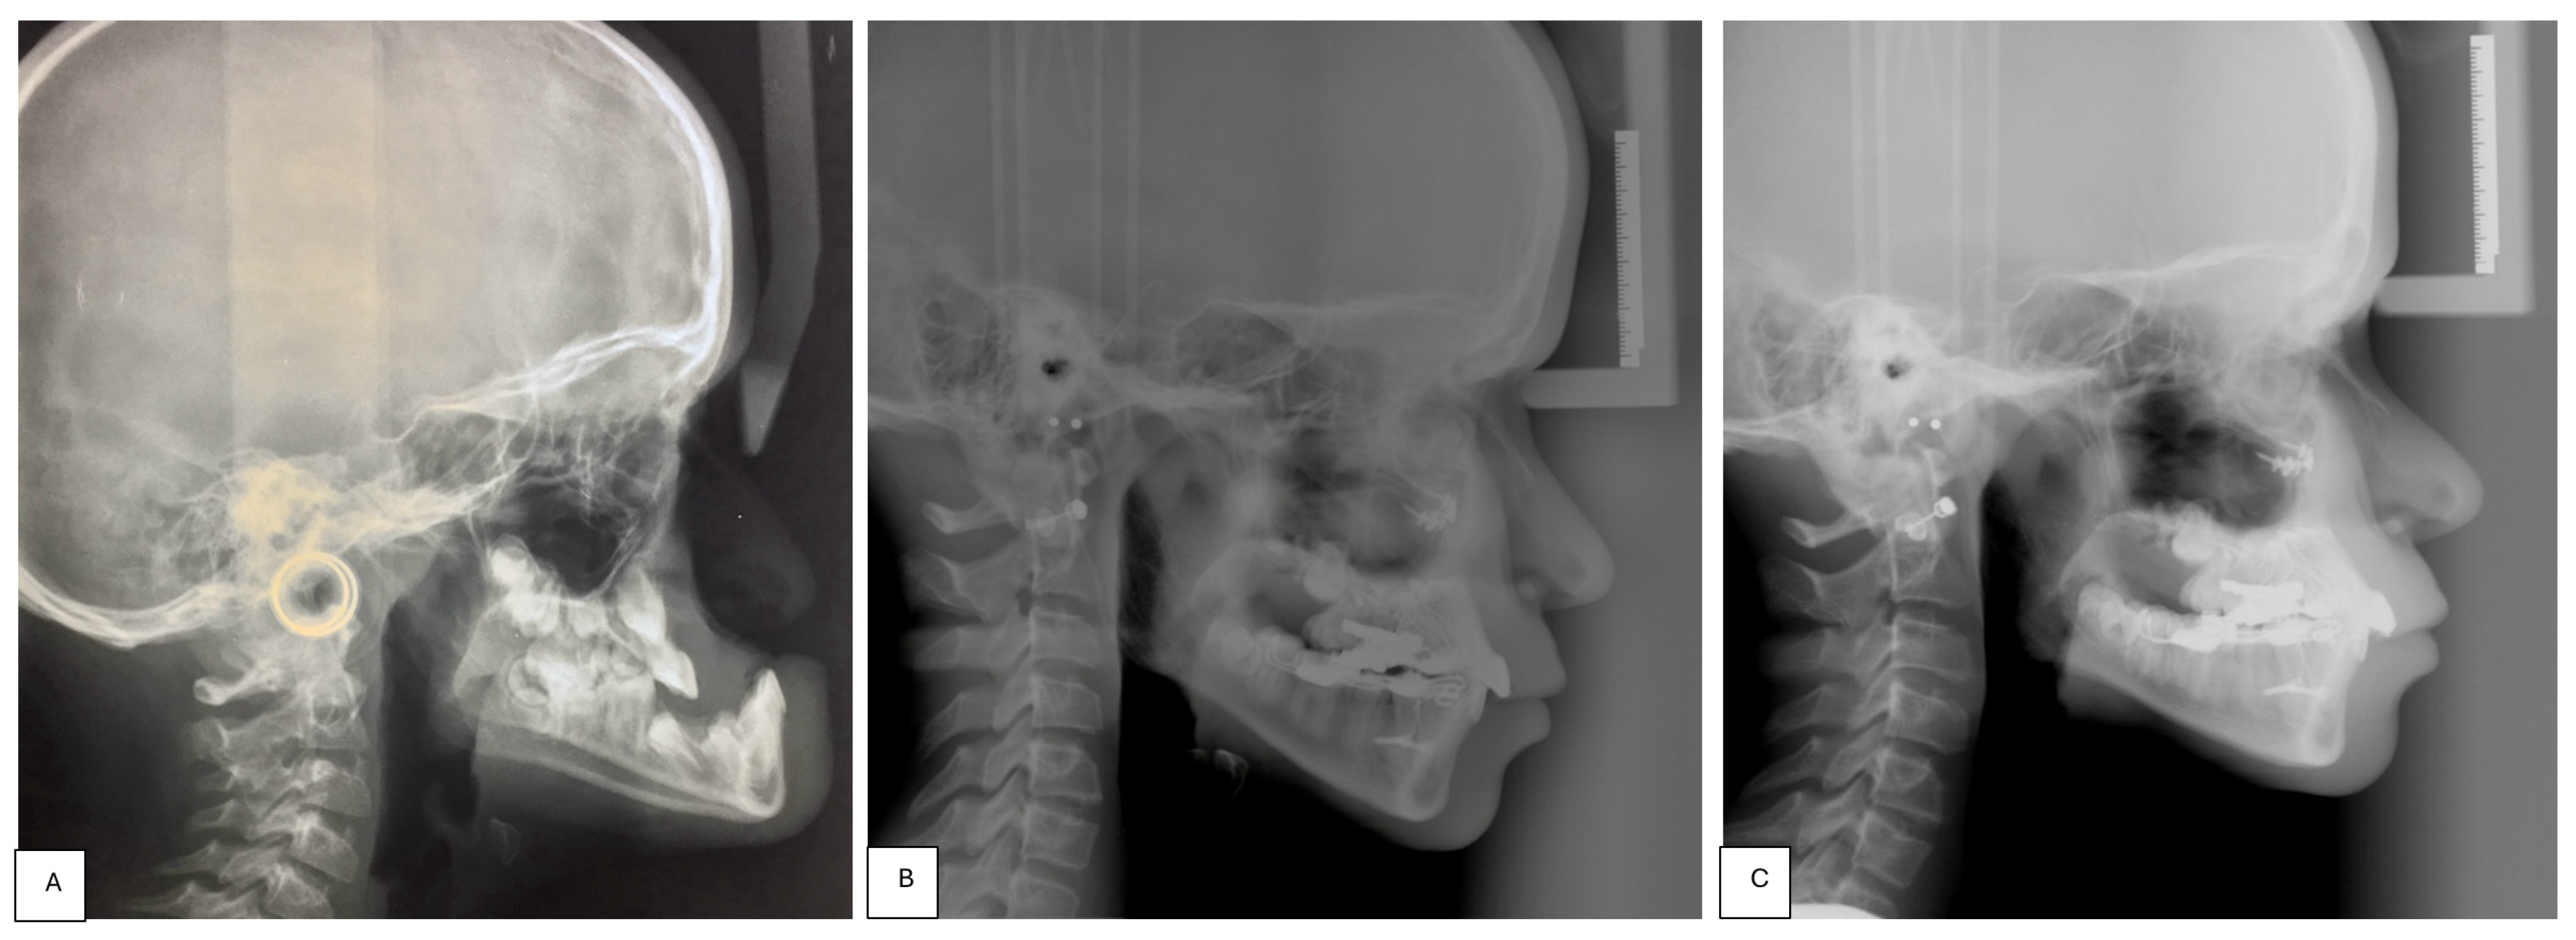

- Placement of an external rigid distractor (RED) during a minor surgery under general anesthesia. The surgical procedure was performed with oro-tracheal intubation through an incision at the level of the upper vestibular fornix with skeletonization of the maxilla. The patency of the zygomatico-maxillary suture was noted. A plate and corresponding screws (Matrix Midface, DePuy Synthes, Raynham, MA, USA) were positioned on each side at the level of the maxillo-malar complex, and two plates, corresponding screws, and percutaneous pins (External Midface Distractor, DePuy Synthes, Raynham, MA, USA) were placed at the level of the lower orbital rim. Percutaneous traction wires were secured to the inferior plates and left protruding at the level of the naso-labial fold. After all intraoral wounds were sutured, the halo was positioned using four cranial screws per side (External Midface Distractor, DePuy Synthes, Raynham, MA, USA). The immediate post-operative period was organized in the Pediatric Intensive Care Unit. As ongoing NIV therapy was critical, the tractions of the RED were positioned in such a way as not to impede the placement of the NIV interface during night (Figure 5).

- Activation of the RED to allow advancement of the midface to overcorrect the dysmorphism. The activation started the day after surgery, 0.5 mm per day. After 4 weeks, the dislodgement of a bone anchorage plate was observed, necessitating an additional intervention to reposition it with a modification of its geometry. The activation continued for 5 additional weeks, for a total of 9 weeks, with an advancement reaching approximately 20 mm at the maxillary level.

- At the end of the distraction phase, after an additional stabilization period of 4 weeks, the RED was removed.